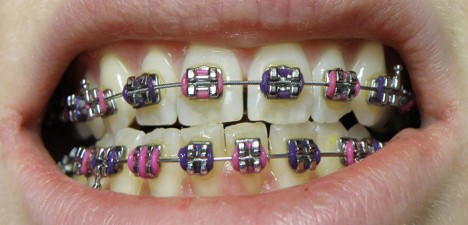

What type of orthodontic appliance is depicted in this image?

Which type of malocclusion is most likely present in this picture?

What is the main component of this type of orthodontic appliance that directly moves the teeth?